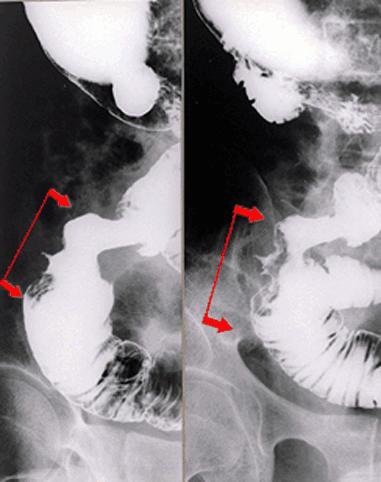

疾患(病理主体)の分類悪性上皮性腫瘍/腺癌

部位(臓器別)小腸/空腸

検査方法X-P

腫瘍の肉眼分類2型(潰瘍限局型)/

病変の最大径(ミリ)40以上

腫瘍の深達度s(a)